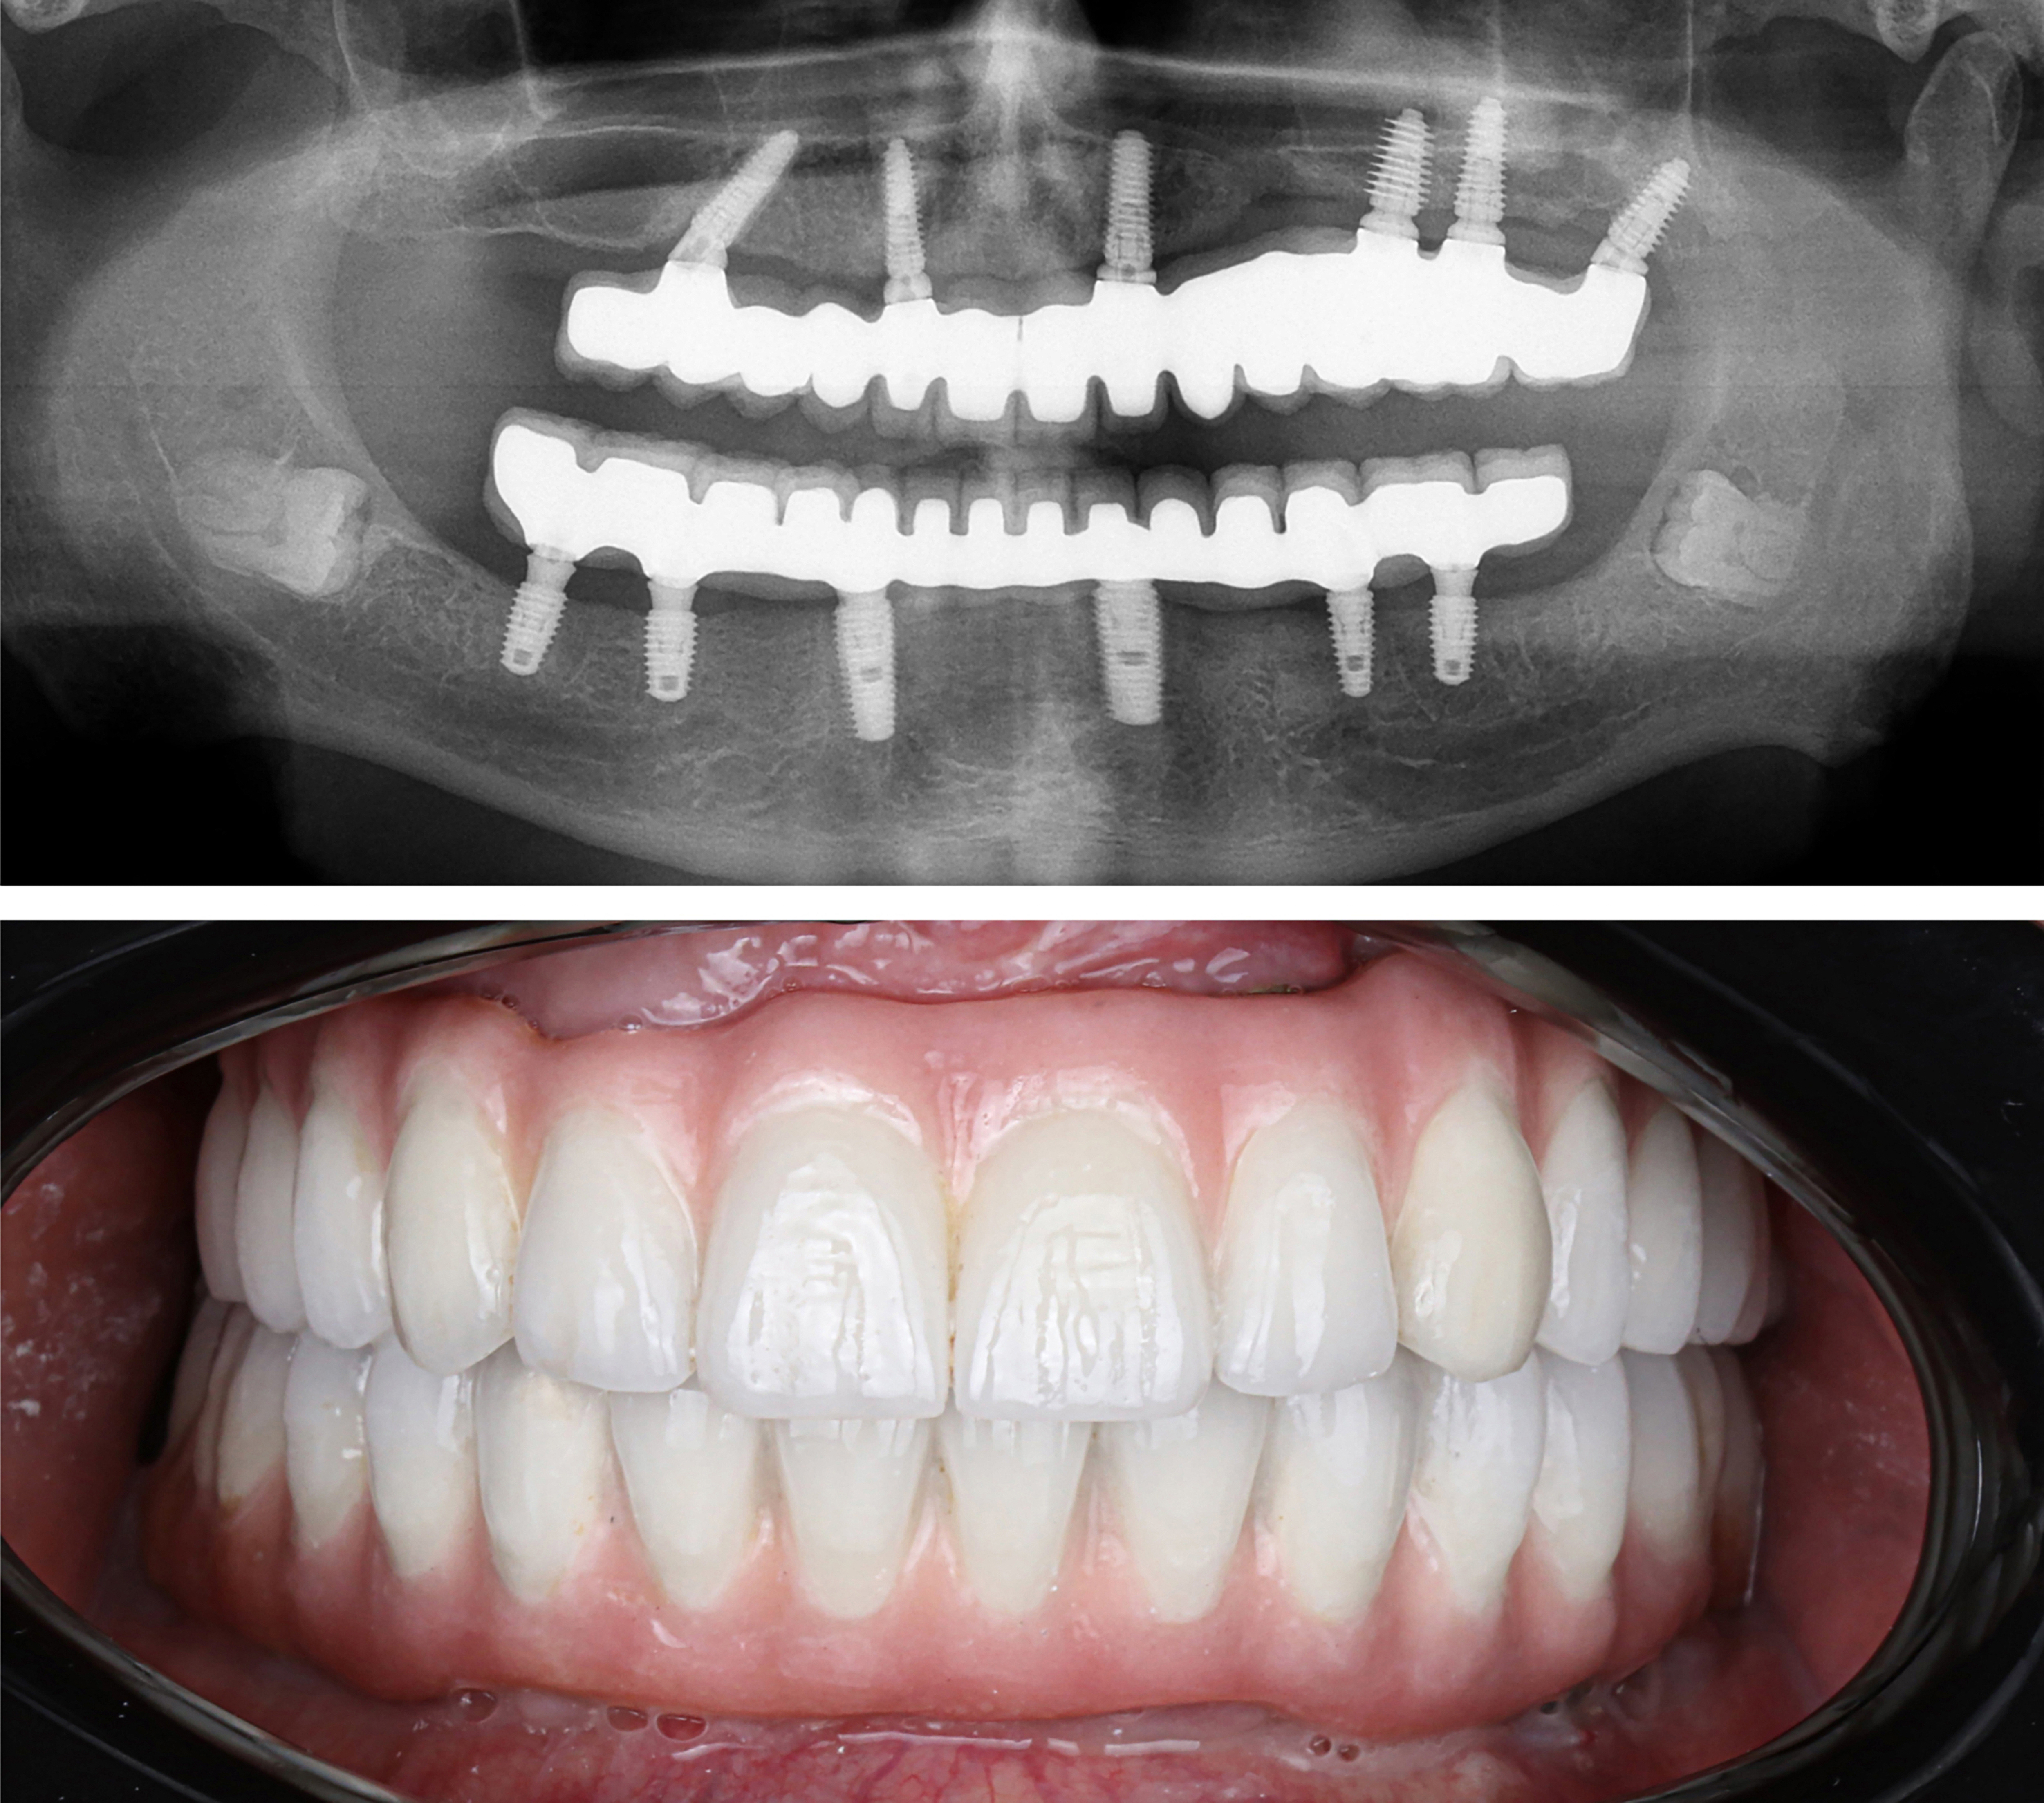

Example transformations achievable with dental implants

Every single dental implant consists of three parts - the implant, the abutment, & the crown. The implant is made of medical grade titanium. This part is surgically placed into the patient’s jaw bone and left to heal for 4-6 months afterwards.

This implant piece acts as the foundation for the rest of the tooth. Once the bone around the site has healed, the abutment and crown are placed on top of the implant. The end result is a beautiful, natural-looking new tooth!

Few people will ever be able to tell the difference between your implants and your real teeth.